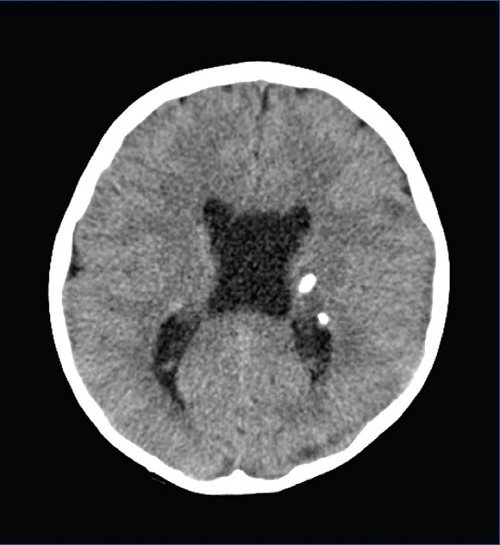

En Urgencias se realizan un análisis sanguíneo y de tóxicos en orina, con resultados normales. Se solicita una tomografía computarizada (TC) craneal (Fig. 1) en la que se identifican lesiones parenquimatosas, la mayoría calcificadas, con distribución periventricular.

Figura 1. TC craneal (corte axial): lesiones parenquimatosas calcificadas periventriculares